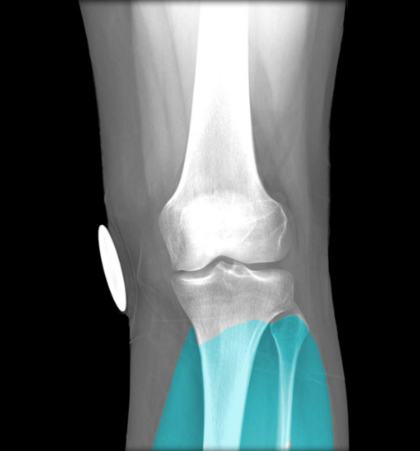

lateral meniscus

knowt flashcard image

anterior cruciate ligament

medial meniscus

Tibial collateral ligament

unhappy triad

ACL, MCL, medial meniscus